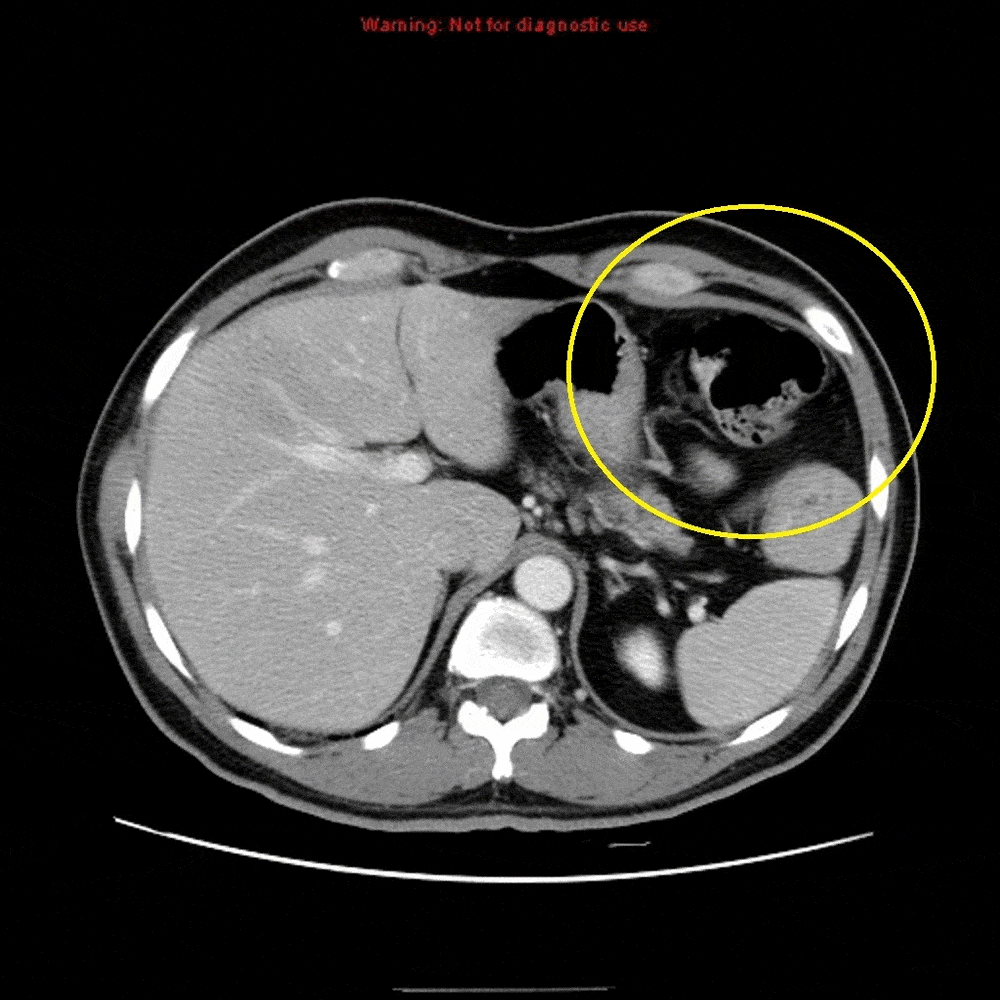

遗憾的是,病情并没有好转,还出现了转移,无论是在骨头上还是在卵巢上,都发现有癌细胞转移过去了。